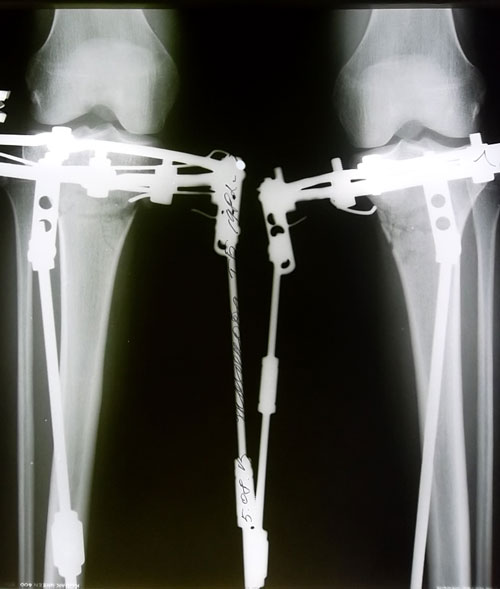

Сегодня 19 день после ОП. Крутки закончились, вчера мы делали рентгеновские снимки. Судя по снимкам кости ровные, левая ножка даже немного иксит, хотя по фото не скажешь. Как будто она все еще кривая.